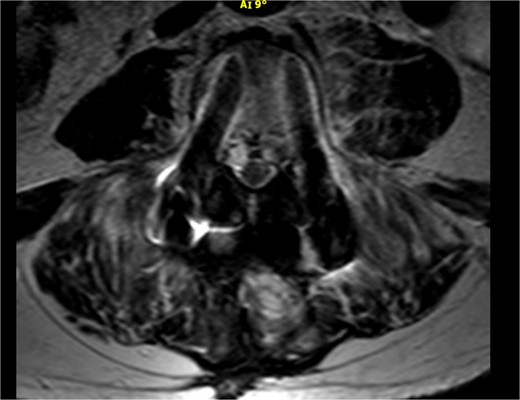

As shown in Table 1, the patient’s blood tests were compatible with infection and an MRI-CT scan was ordered to confirm or exclude the participation of lumbar spine. Subsequently, the MRI revealed signs compatible with the diagnosis of osteomyelitis involving the L4 and L5 vertebra as shown in sagittal view in Fig. 1 where screws were placed, with the presence of pathological collection of fluid around the pedicle screws and diffuse soft tissue edema as shown in the axial view in Fig. 2. Additionally, the CT scan revealed septic loosening of the pedicle screws. Immediately the patient underwent surgical irrigation and debridement with placement of new larger pedicle screws due to the absence of union. Intraoperatively eight different samples were collected for culture from the surrounding soft tissue and bone, while the previous pedicle screws were sent for sonication. Postoperatively all the blood cultures were negative along with the soft tissue and bone, only the sonication revealed infection with P. asaccharolyticus

Axial view of the MRI scan demonstrating pathological fluid collection around the pedicle screws.